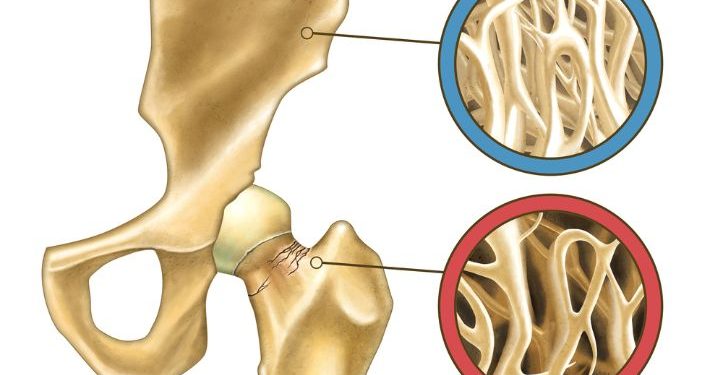

Bone metastasis is most commonly seen in the spine (vertebrae), pelvis, upper leg bone (femur), humerus, and ribs, but it can occur in any bone in the body. The most common type of bone metastasis is osteolytic, which means that cancer cells break down the bones and release the mineral into the bloodstream. This makes the bone softer and weaker, which increases the risk of breaking or other complications.